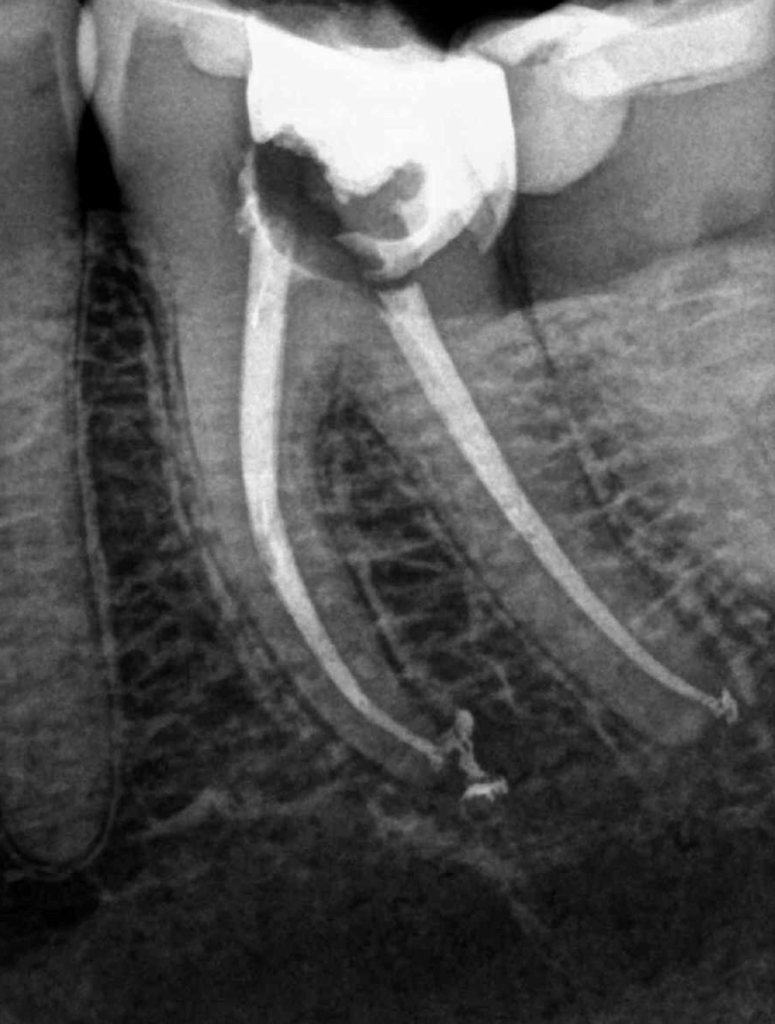

Molar gran curvatura bifurcación palatino